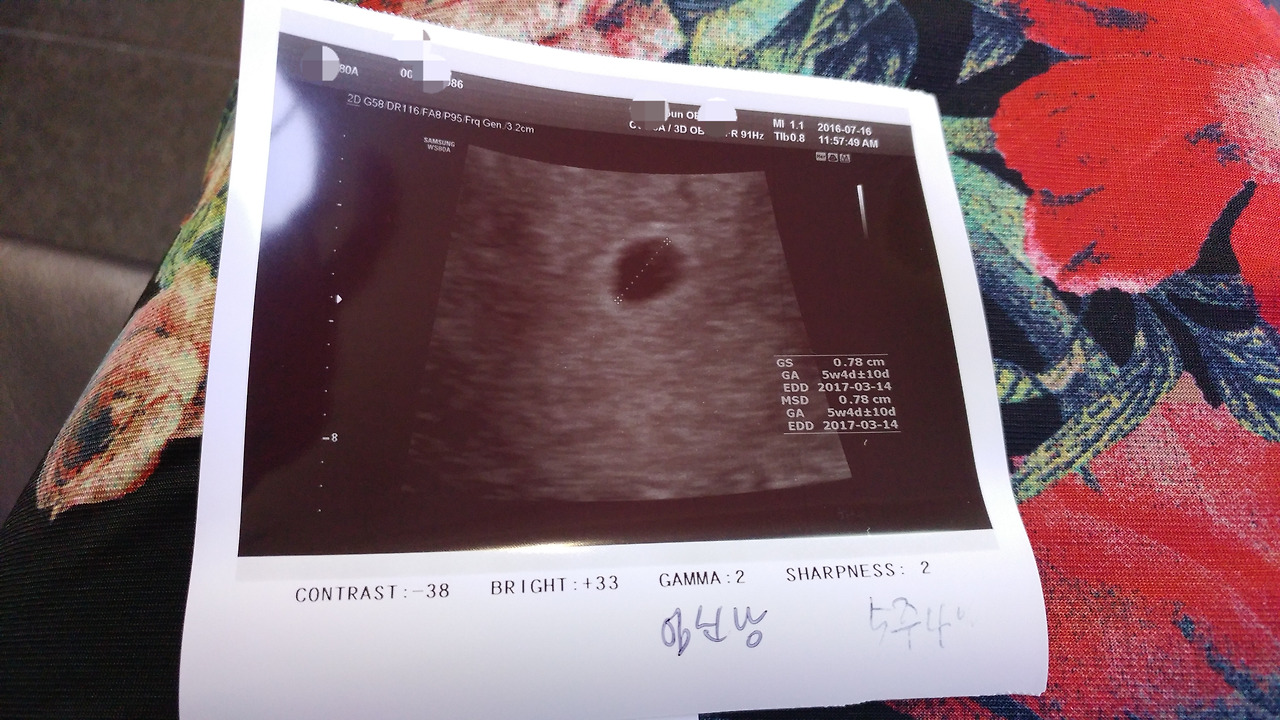

임신테스트기로 두줄을 확인하자마자 남편과 함께 곧바로 산부인과로 갔다. 선생님은 5주 4일 정도 되었다고 하셨고 건강검진받은 것과 감기약 먹은 것은 별 신경 쓰지 않아도 된다고 하셨다.

5주 4일 된 둘째